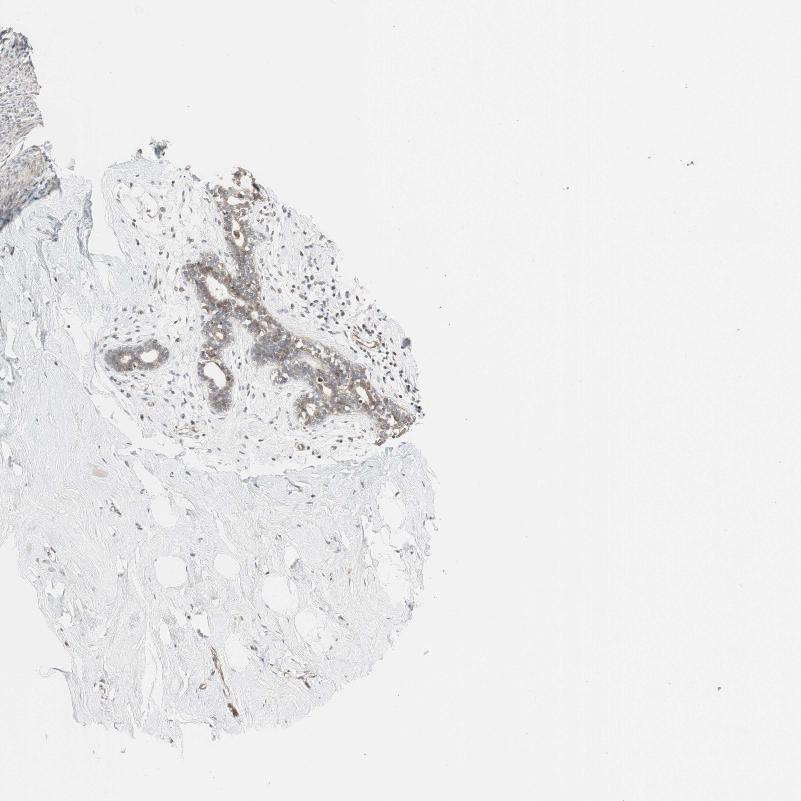

BREAST - Antibody stainingi

Antibody staining in the annotated cell types in the current human tissue is reported as not detected, low, medium, or high, based on conventional immunohistochemistry profiling in selected tissues. This score is based on the combination of the staining intensity and fraction of stained cells.

Each image is clickable and will lead to virtual microscopy that enables deeper exploration of all samples and also displays staining intensity scores, fraction scores and subcellular localization as well as patient and tissue information for each sample.

Antibody HPA005709

Adipocytes Not detected

Glandular cells Low

Myoepithelial cells Not detected